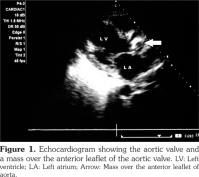

Cardiac involvement in granulomatosis with polyangiitis is rare. In this article, we describe a 47-year-old male case of aortic valve involvement with granulomatosis with polyangiitis. The patient had multi-system involvement in the form of pulmonary, renal, cutaneous involvement along with high levels of anti-proteinase 3. Echocardiography revealed a mass over the anterior leaflet of aortic valve with a mild aortic stenosis and aortic regurgitation. We suggest that clinicians should perform a thorough cardiac examination for any possible valvular involvement in patients with granulomatosis with polyangiitis.

The patient had normocytic normochromic anemia with a hemoglobin level of 8 g/dL, white blood cell count of 14000/mm3 with 80% neutrophils, serum urea value of 80 mg/dL, and serum creatinine value of 2.5 mg/dL. Serum electrolytes and liver function test results were normal. Urinalysis examination revealed protein 3+, and 15-20 red blood cells per high power field. Twenty-four-hour urine protein was 1.2 grams. Abdominal ultrasound revealed enlarged kidneys with increased echotexture and altered corticomedullary differentiation. Thoracic X-ray demonstrated bilateral pulmonary infiltrates, while computed tomography revealed bilateral patchy opacities with thickening of the right horizontal fissure and bilateral alveolar infiltrates. Echocardiography also revealed a mass over the anterior aortic valve with mild aortic stenosis and moderate aortic regurgitation (Figure 1). Anti-neutrophilic cytoplasmic antibody (ANCA) serology showed a markedly increased level of anti-proteinase 3 (anti-PR3) (31 IU/ml, cut off ≤3.5 IU/ml), and anti-myeloperoxidase (anti-MPO) level of 2.1 IU/ml (cut off ≤9 IU/ml). Blood cultures were sterile. Antinuclear antibodies, human immunodeficiency virus, hepatits B surface antigen, hepatitis C virus serologies and sputum for acid-fast bacilli were negative. A preliminary diagnosis of GPA with acute nephritis and probable alveolar hemorrhage were made based on the possibility of concomitant infective endocarditis/involvement due to GPA. The patient was firstly treated with broad-spectrum antibiotics. However, after three days of no response to the antibiotic therapy, the patient was started on pulse methylprednisolone doses of one gram per day for five days along with pulse cyclophosphamide of 750 mg, and the antibiotics were also continued. The patient improved over a period of one week, and his hemoptysis stopped. His repeat urea was 60 mg/dL, and serum creatinine level was 1.5 mg/dL. The patient was discharged with prednisolone 60 mg per day and was asked to apply to the outpatient department for the next pulse of cyclophosphamide. However, the patient did not report back and was lost to follow-up.

Our patient presented with predominantly renal and pulmonary involvement. Besides, in the course of investigation, he was found to have a valvular lesion in the form of aortic valve mass. We considered the possibility of the mass being a vasculitic lesion in view of the patient’s high disease activity in other organs including the lungs, kidneys and skin, and high titers of anti-PR3 antibodies. Additionally, no organism grew in blood cultures, and the patient responded to high doses of parenteral steroids.